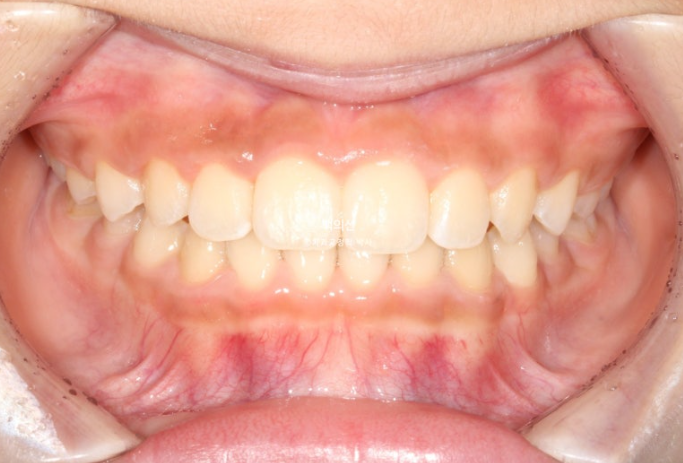

이제 남아있는 유치는 없고 모든 영구치가 제자리에 예쁘게 나왔습니다.

25.07

물샐틈 없는 1급 교합관계를 보입니다.

결과가 성인 2차교정결과에 준하는 만큼 유지장치도 성인교정 유지장치와 동일하게 들어갑니다.

1차 세트 6개월 치료, 9개월간 휴식기, 7개월간 2차세트 치료를 거쳐 마무리된 모습입니다.

덧니와 과개교합의 개선입니다.

23.07~25.07

앞니 돌출의 개선

교합의 개선